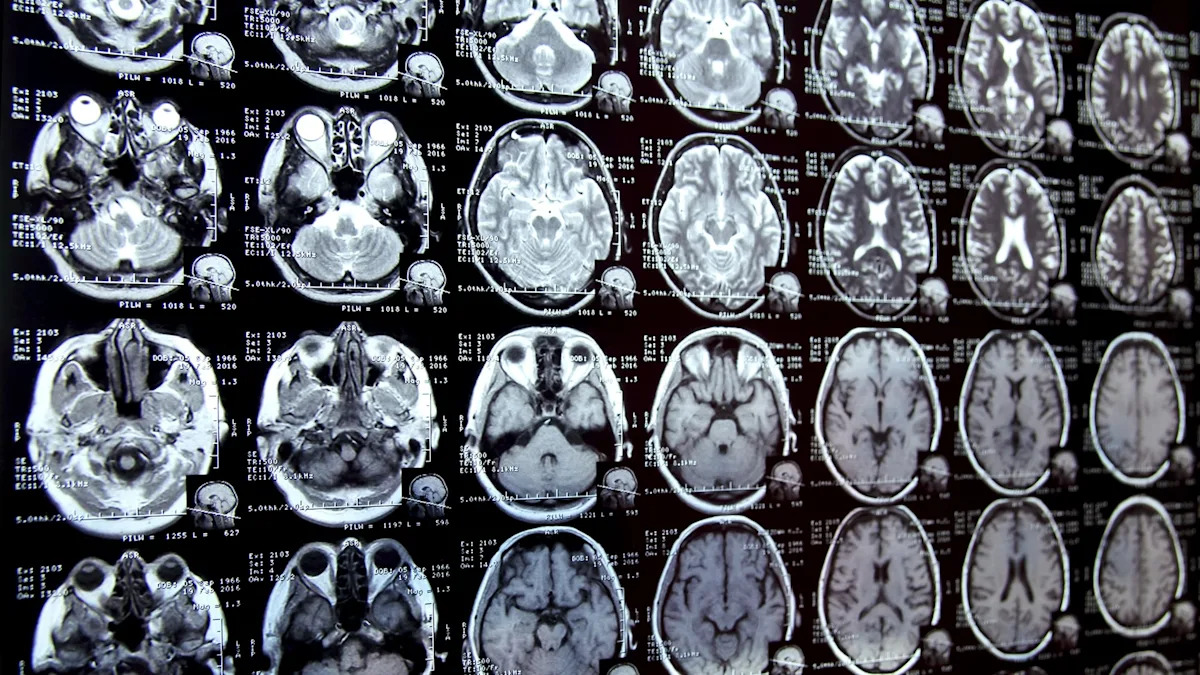

لم يعد التلوث البلاستيكي مجرد مشكلة تتعلق بالمحيطات بعد الآن، بل أصبح أقرب بكثير إلى المنزل مما قد تعتقد. كشفت دراسة حديثة أن الدماغ البشري العادي قد يحتوي على ما يعادل خمس أغطية زجاجات بلاستيكية من اللدائن الدقيقة.

وفي دراسة رائدة أجراها باحثون في جامعة نيو مكسيكو، وجد العلماء أن عينات الدماغ من عام 2024 تحتوي على ما يقرب من 50% من المواد البلاستيكية الدقيقة أكثر من تلك التي تم جمعها قبل ثماني سنوات فقط. يحتوي الدماغ المتوسط ​​على ما يقرب من سبعة جرامات من البلاستيك، وهو ما يعادل ملعقة يمكن التخلص منها.

والأمر الأكثر إثارة للقلق هو أن الباحثين لاحظوا مستويات أعلى من المواد البلاستيكية الدقيقة في أدمغة الأشخاص المصابين بالخرف، على الرغم من أن العلماء في المختبر، كما أشارت التايمز، “لاحظوا أن ذلك قد يكون بسبب أن تلك الأدمغة لديها حاجز دموي دماغي أكثر مسامية وأقل قدرة على إزالة السموم”. وقد تم بالفعل العثور على جزيئات بلاستيكية مماثلة في المشيمة البشرية، ومجرى الدم، وحتى في البراز الأول للطفل.

بمجرد دخولها جسم الإنسان، تكون بعض جزيئات البلاستيك صغيرة جدًا بحيث يمكنها المرور عبر الحواجز الحرجة وتستقر في أعضاء مثل الدماغ. في حين أن العلماء لم يحددوا بعد مقدار البلاستيك الذي يعتبر أكثر من اللازم، إلا أن نتائج الأبحاث المبكرة تشير إلى ما لا يقل عن خطورة.

تُظهر الأبحاث الحالية روابط بين المواد البلاستيكية الدقيقة والقضايا الصحية الخطيرة، بما في ذلك التدهور المعرفي، والمخاوف الإنجابية، واختلال جهاز المناعة، وفقدان الذاكرة، والاضطرابات الهرمونية، وحتى مشاكل النمو لدى الأطفال. ولأن معظم هذه النفايات البلاستيكية عمرها عقود من الزمن، فهي ليست مجرد مشكلة مستقبلية – إنها موجودة بالفعل.

وأشار البحث العميق الذي أجرته صحيفة التايمز، والذي يحتوي على العديد من التفاصيل الرائعة، إلى أن فريق الدكتور كامبدن يواصل أبحاثه و”يدرس الآن الأنسجة من مقاطع عرضية من دماغ واحد لمعرفة ما إذا كانت مناطق معينة تحتوي على تركيزات أعلى من المواد البلاستيكية الدقيقة وما إذا كان يمكن ربط ذلك بمشاكل مثل مرض باركنسون أو فقدان الذاكرة”.